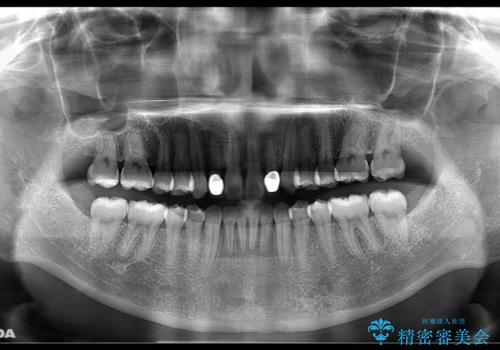

- 上の前歯が大きい事と下の前歯のがたつきを気にされてご相談にいらした方です。上の2番目の歯が矮小歯であったため、矯正治療にて歯のスペースを作った後、矮小歯には被せ物をして前歯のバランスを整えました。

矯正治療と補綴治療をうまく組み合わせることで、美しい口元に仕上げることが出来ました。矯正治療、補綴治療をまとめて行える総合歯科治療を体現した治療といえます。